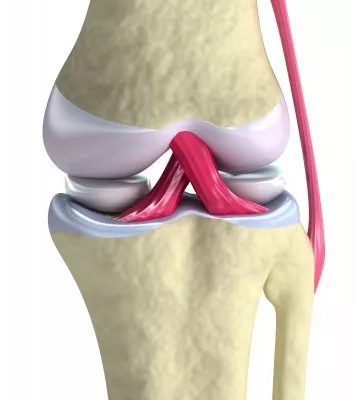

#3 Poškodba sprednjih križnih vezi

Poškodba sprednje križne vezi je v Sloveniji najpogostejša poškodba vezi kolena. Večina teh poškodb nastane pri športnikih brez kontakta (72-95%), pri hitri spremembi smeri ali doskoku na iztegnjeno koleno. Sprednja križna vez stabilizira koleno v polnem iztegu in preprečuje hiperekstenzijo ter preveliko zunanjo rotacijo. Mehanizem poškodbe sprednje križne vezi lahko razdelimo na kontaktni in nekontaktni mehanizem. Dejavniki tveganja za nastanek poškodbe sprednje križne vezi so intrinzični (leta, spol, predhodne poškodbe, hormonski vplivi, velikost interkondilarne zareze), ekstrinzični (človeški faktor, obutev, zaščitna oprema) in kombinirani (okvarjena propriocepcija).

Pri poškodbi kolenskega sklepa se zelo redko zgodi, da se poškoduje samo sprednja križna vez. Najbolj pogosta pridružena poškodba je poškodba medialnega meniskusa. Klinični pregled je najpomembnejši del diagnostike. Pri kliničnem pregledu se opravijo štirje najbolj pogosti testi: Lachman test, sprednji predalčni fenomen, Pivot-shift test in merjenje pomika golenice naprej z altrometrom. Poškodovano sprednjo križno vez je mogoče zdraviti na operativni in konzervativni način. Namen uspešnosti konzervativnega zdravljenja sprednje križne vezi ni le vrnitev funkcionalne stabilnosti kolenskega sklepa, ampak tudi preprečitev nadaljnjih poškodb. V protokolu konzervativnega zdravljenja se najpogosteje izvajajo izometrične vaje, vaje za mišico kvadriceps, koncenrtične vaje za mišico kvadriceps in fleksorje kolena, uporaba električne stimulacije za povečanje moči mišice kvadriceps in fleksorje kolena, trening sklepne stabilizacije ter tek po ravni podlagi in kolesarjenje. Pri izvajanju programa za povečanje moči mišic je bolj potrebno krepiti mišice fleksorje kolen kot pa mišico kvadriceps.